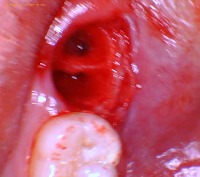

These are two intraoral photos of what both of the extraction sockets that the two teeth came from: